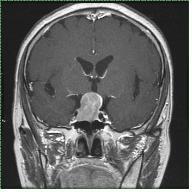

수막종은 축외 뇌종양 중 가장 발생빈도가 높은 종양으로 원발 뇌종양의 약 25%를 차지합니다. 주로 40~50대 성인에 많이 발생하고 2:1의 비율로 여자에게서 더 많이 발생한다고 알려져 있습니다. 수막종은 수술만으로 완치될 가능성이 매우 높은 양성종양으로, 뇌를 지지하는 뇌막인 수막(meninges)의 구성 성분인 지주막세포에서 기원한다고 알려져 있습니다. 수막종은 지주막 세포가 분포한 곳에서는 어디서나 발생하지만, 이들 세포의 밀도가 높은 시상 정맥동 주변, 대뇌궁륭부, 뇌바닥, 후두개와 등에서 더 빈번하게 발생합니다.

수막종은 성장 방식 및 종양의 성상에 몇 가지 특징을 가집니다. 이 종양은 대부분 뇌경막에서 발생하여 딱딱한 두개골 때문에 밖으로 자라지 못하고 거의 항상 뇌조직 쪽으로 자랍니다. 그러나 침습적인 성장이 아니어서 뇌조직과 종양 사이에 연뇌막은 물론 뇌척수액을 포함한 지주막이 대부분 잘 보존되며, 이로 인해 신경학적 장애를 초래하지 않고 종양을 절제할 수 있습니다. 종양 자체는 단단하고 혈관분포가 풍부한 것이 특징입니다.